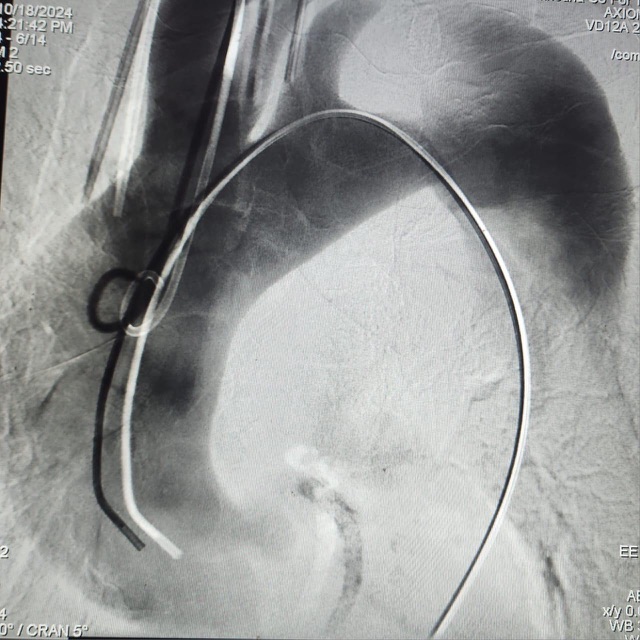

وأشار البيان إلى أنه على الفور اجتمع فريق جراحة الأوعية الدموية بالمستشفى لدراسة الحالة، وجرى تحديد الإجراءات الطبية اللازمة، وتم إتخاذ قرار اجراء الجراحة بتقنية التيفار TEVAR.

ويعد هذا النوع الحل الأمثل لتلك الحالات، ما يعني أنه يعتمد على استخدام القسطرة التداخلية، من خلال شقوق جراحية صغيرة، والتي تساعد بدورها على تخفيف ألم الصدر والأعراض الأخرى، وتم التواصل مع شركات توريد تلك الدعامات لتحديد قياسات الدعامات اللازمة للحالة بدقة وتجهيزها.

وأوضح البيان، أنه تم إجراء الجراحة للسيدة عن طريق تركيب دعامات مغطاه بالشريان الأورطى بالصدر، باستخدام القسطرة التداخلية مع توصيل الشريان السباتي الأيسر بالشريان تحت الترقوة اليسرى جراحيا باستخدام شريان صناعي.